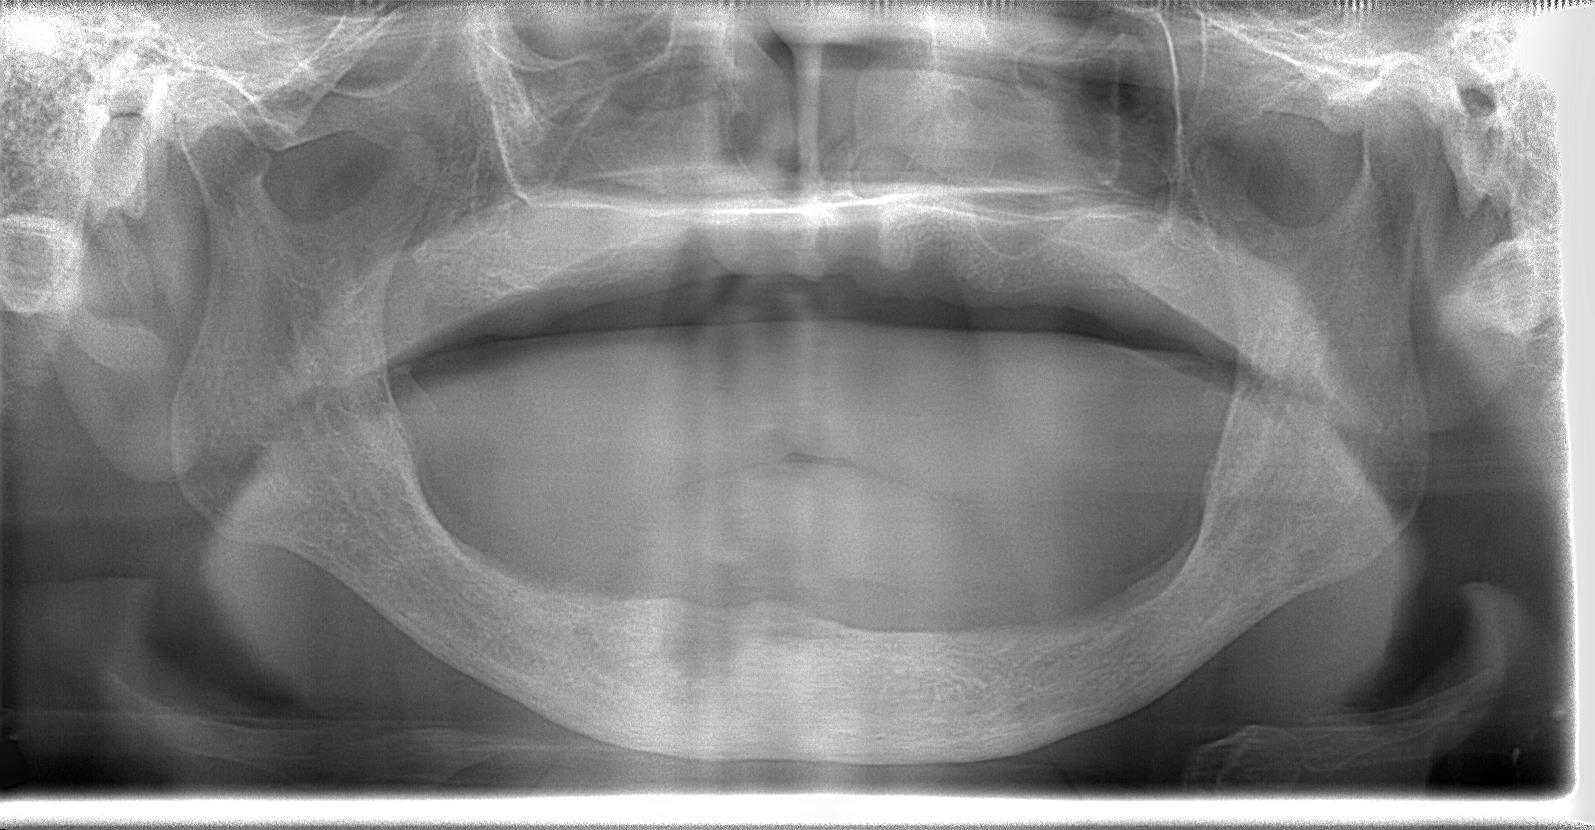

術前パノラマレントゲン写真